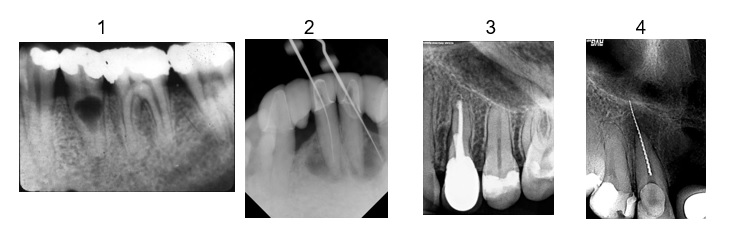

Które z poniższych zdjęć rentgenowskich przedstawiają perforację wierzchołkową?